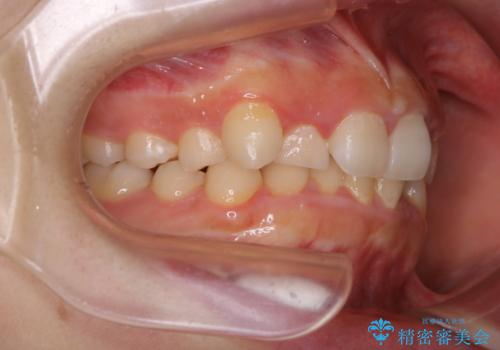

前歯のがたつきとディープバイト:インビザライン治療

- 前歯のがたつきと、噛み合わせが深いことを気にされてご相談にいらした方です。

インビザラインにて治療を行いました。

一般的に、歯冠(歯の長さ)が短い方はインビザライン治療に時間がかかりやすい傾向にあります。

歯の移動量に対して大きなブラックトライアングルもできることなく綺麗に並べることができ、大変喜んでいただけました。